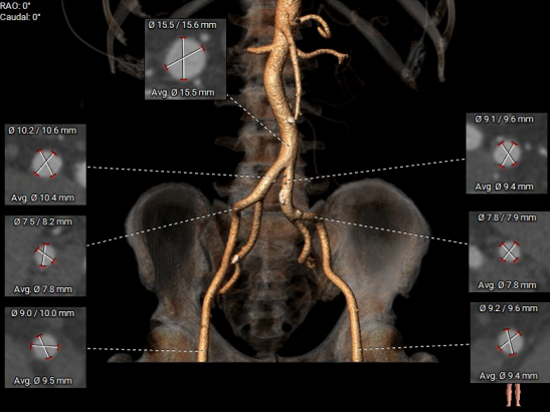

CT测量

主动脉根部CT测量

瓣环周长:73.1mm

LVOT周长:79.3mm

瓣环上4mm:71.2mm

瓣环上6mm:70.4mm

左冠开口高度:7.1mm

右冠开口高度:13.7mm

左窦瓣叶长度:15.2mm

右窦瓣叶长度:16.6mm

STJ周长:88.6mm

升主动脉周长:112.3mm

法氏窦

右冠状窦直径:28.8mm;左冠状窦直径:30.8mm;无冠状窦直径:32.5mm

入路情况

双侧入路CT测量

入路双侧血管迂曲